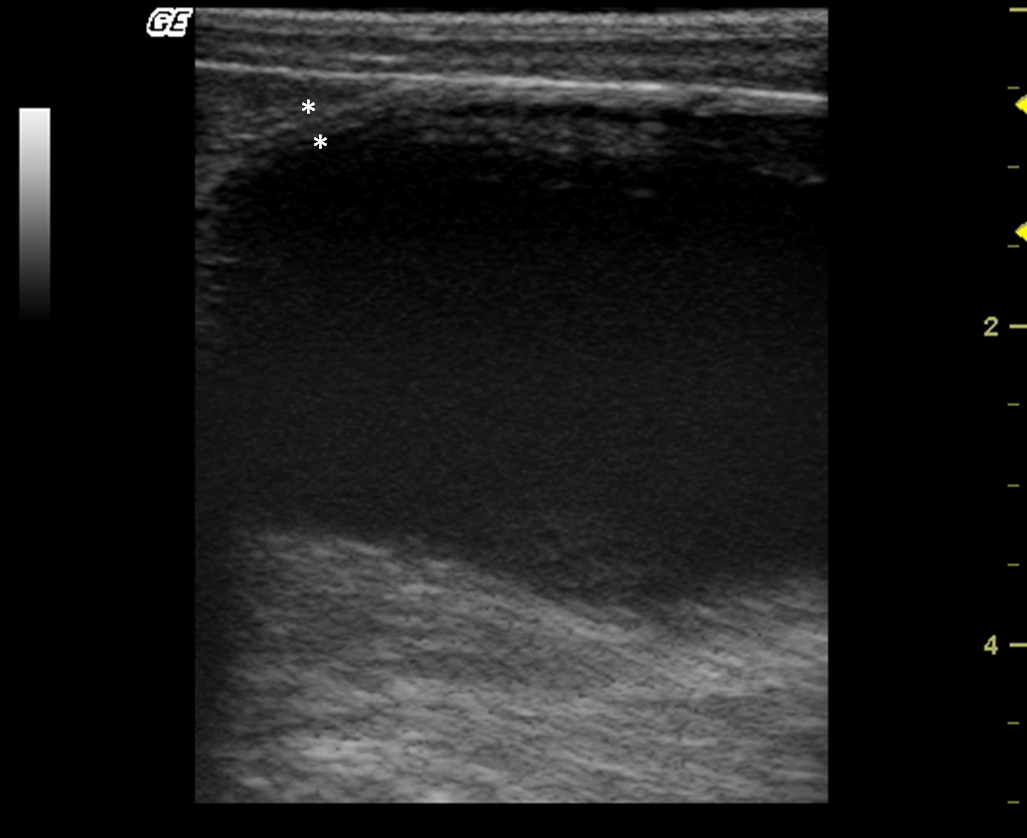

The kidneys were observed in the retroperitoneal space. The left kidney was evaluated caudal to the gastric fundus and the right was identified in the renal fossa of the right liver in all individuals. Kidneys lengths (average of 3.81 cm), are described in Table 1. The renal outlines were well defined and regular, delineated by a thin hyperechogenic line, the renal capsule (Fig. 2a,b). It was possible to identify and delineate the cortical, medullary and renal pelvis regions in all individuals. The cortex showed homogeneous echotexture and it was isoechoic to hyperechoic to the liver parenchyma and isoechoic when compared with the splenic parenchyma. The medullary region was well defined and appeared hypoechogenic in relation to the cortex. The pelvis was hyperechoic in relation to other parts of the kidney, possibly due to the fat present in this region. Discrete pyelectasis (0,2–3 mm) was observed in at least one kidney in five monkeys. This finding is assumed to be due to the fluid therapy or a normal variant. The relationship among cortical and medullary regions was measured, averaging proportion of 1:1. Post-mortem study of the kidneys allowed a better understanding of the anatomy (Fig. 2c,d). Medullary rim sign was not observed in any individual.

Figure 2.

(a,b) Sonogram of the kidney in frontal (a) and sagittal (b) image planes. (c,d) Post-mortem comparative study of the kidney on a frontal view (c) and sagittal view (d). 1 – Cortical, 2 – Medullar, 3 – Renal pelvis.